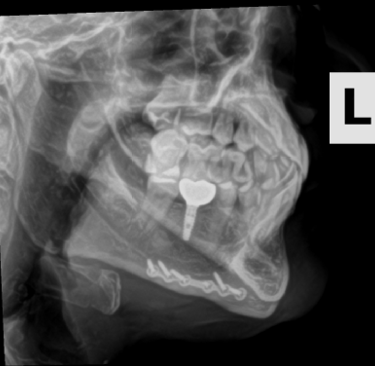

The story of how I got the x-ray or at least the whole scenario was kind of funny. I broke my pinky somehow at my friend's house in Oklahoma in the fall of 2023. When I went to the doctor they did an x-ray of my hand. I have a few metal parts in my head and then told them I got into a fight and thought I may have hurt some implants in my head. Not really but I just wanted these X-rays.